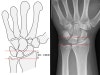

1. Ulnar variance

1) Ulnar variance refers to the position of the cortical margin of the distal ulna relative to that of the distal radius.

2) 60% of the population are ulnar neutral.

3) If < 0 mm then negative ulnar variance, associated with keinbock disease

If > 0 mm then positive ulnar variance, associated with ulnar abutment syndrome

2. Radial height

1) The distance between one line perpendicular to the long axis of the radius passing through the distal tip of the radial styloid.

2) A second line intersects distal articular surface of ulnar head.